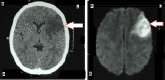

Takayasu's arteritis is a chronic inflammation of the large arteries such as the aorta and its primary branches, causing progressive arterial occlusion. This leads to reduced blood flow in the limbs and organs, resulting in arm or leg claudication, diminished or absent peripheral pulses, and end-organ ischemia. Stroke is one of the common complications; however, it is rarely the initial presentation. We describe one such case of a 16-year-old female, who presented with right-sided hemiparesis and non-fluent aphasia, without any significant past history. On examination, her right arm was cold and pulseless. She was extensively investigated for the cause of her presentation. Only non-specific inflammatory markers such as erythrocyte sedimentation rate (ESR) were elevated. Imaging studies revealed left middle cerebral artery territory infarct with occlusion of common carotid arteries, bilateral bifurcation, most parts of the left internal carotid artery, and the proximal part of the right internal carotid artery. She was diagnosed with Takayasu's arteritis and was prescribed steroids, on which she gradually recovered and was discharged. In conclusion, young patients, who present with stroke, should be investigated for Takayasu's arteritis, which leads to earlier treatment and prevention of further life-threatening end-organ damage.